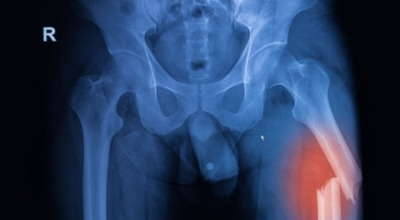

콘드로이친은 주로 골관절염 증상 관리를 위한 치료제로 사용되고 있습니다. 미국에서 골관절염 환자 604명을 대상으로 한 연구에서 콘드로이친의 골관절염 통증 관리 효과를 관찰한 결과, 무릎 골관절염 통증이 있는 사람들 중 약 10%가 통증 완화와 개선 효과를 경험하였습니다. 그 이유는 노화가 진행되는 중장년층에서 콘드로이친 수치가 저하되는 것을 확인할 수 있기 때문입니다.

이는 곧 연골이 뼈와 뼈 사이에서 완충 및 보호 기능이 약화되는 것으로 이어지는데, 이를 보충하면 관절염 개선에 도움이 됩니다. 또한 콘드로이친은 관절 세포 재생에 도움을 주며 외부 충격을 흡수하고 완화하는 데에도 효과가 뛰어납니다.